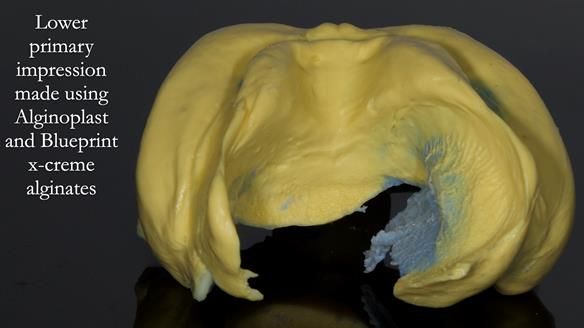

Because her denture space anatomy was limited, I took two working impressions at the same visit. She had very little space in the lower jaw because of the spread of the tongue and the fact she had never worn a lower denture. This made it difficult to judge exactly where the borders needed to be and how much functional space we truly had.

The first impression was my usual Dr Abe shaped impression, which forms the base of my complete denture protocol.

I then made a second working impression using Dr John Besford’s neutral zone approach, known as the French Impression Technique. John learnt this from a dentist in Marseille called Hubert Aiche. I used this technique to record the functional position of the denture borders and tooth space in case the conventional method did not give a stable enough shape.

Both records were processed and compared.

In Sheila’s case, the Dr Abe shaped impression gave a more stable and comfortable result. Sheila preferred the shape produced by the Abe method, so that is the one we used for the registration rims, the trial denture and the final dentures. But making both impressions was worthwhile. It meant we had every option covered and could choose what worked best for her mouth.